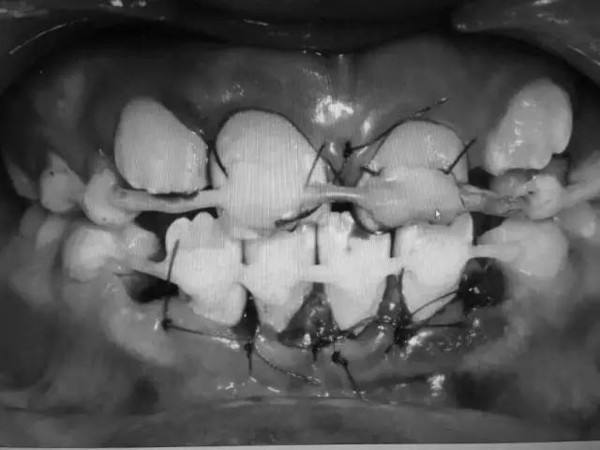

乳牙的牙根和牙冠长度有限,不能满足固位要求,再加上牙槽骨骨折,牙龈撕裂伤严重,给本就复杂的治疗又增加了难度,只能通过牙龈悬吊外伤松动牙,初步稳固,再尝试固定。

为此,盛迪特意在治疗方案中增加了牙龈乳头复位这个环节,将已经完全倾倒的牙龈乳头一点一点地翻开,推回到正常位置,再小心翼翼的进行缝合,固定,既要止血还要保障血供,防治坏死。缝合牙龈的同时复位固定松动牙。

整个过程,花了2个多小时。

有同事笑谈,“这个病例,让盛老师练起了针线活儿”。